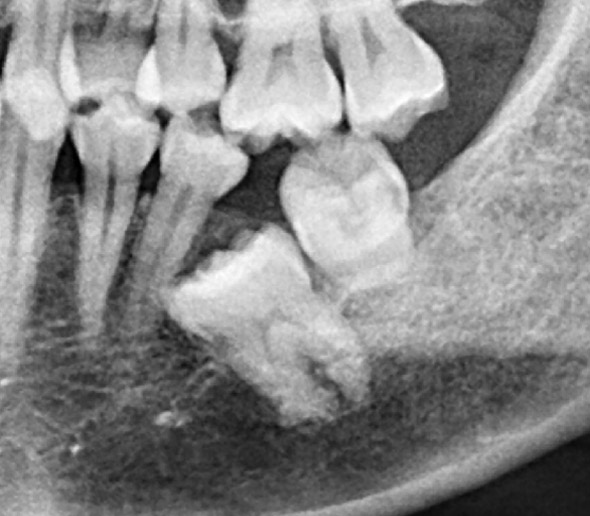

本院為40年 口腔外科專業診所,主攻”安全、無痛”、專拔高風險(牙根與神經交錯或緊貼)、高難度、深度阻生智齒手術。

外面一顆要拔兩個小時,本院一顆十分鐘

外面拔時易斷裂於骨頭內而難以取出